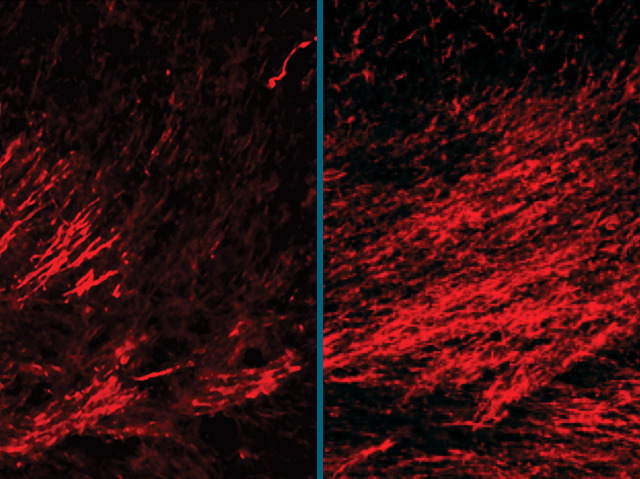

Rescuing Brain Cells

When a child’s born too soon, their lungs are often underdeveloped. As a result, the brain experiences damaging oxygen deprivation, killing cells. A brain injury of this type affects development of the infant’s sensory and motor nerves, causing lasting difficulties with learning and movement. By studying this kind of damage in a mouse model, the scientists knew that a molecule called EGF is crucial for the brain’s white matter cell development. Now they've tested whether increasing the amount of EGF in the cells can help repair damage. After birth, many cells have died in the suffocated white matter pictured on the left. But when EGF is enhanced damaged cells recover – more of the red-stained nerve fibres are visible (right) – looking like healthy brain tissue. The EGF was delivered by nasal spray. It could be a simple way of treating affected children in future.